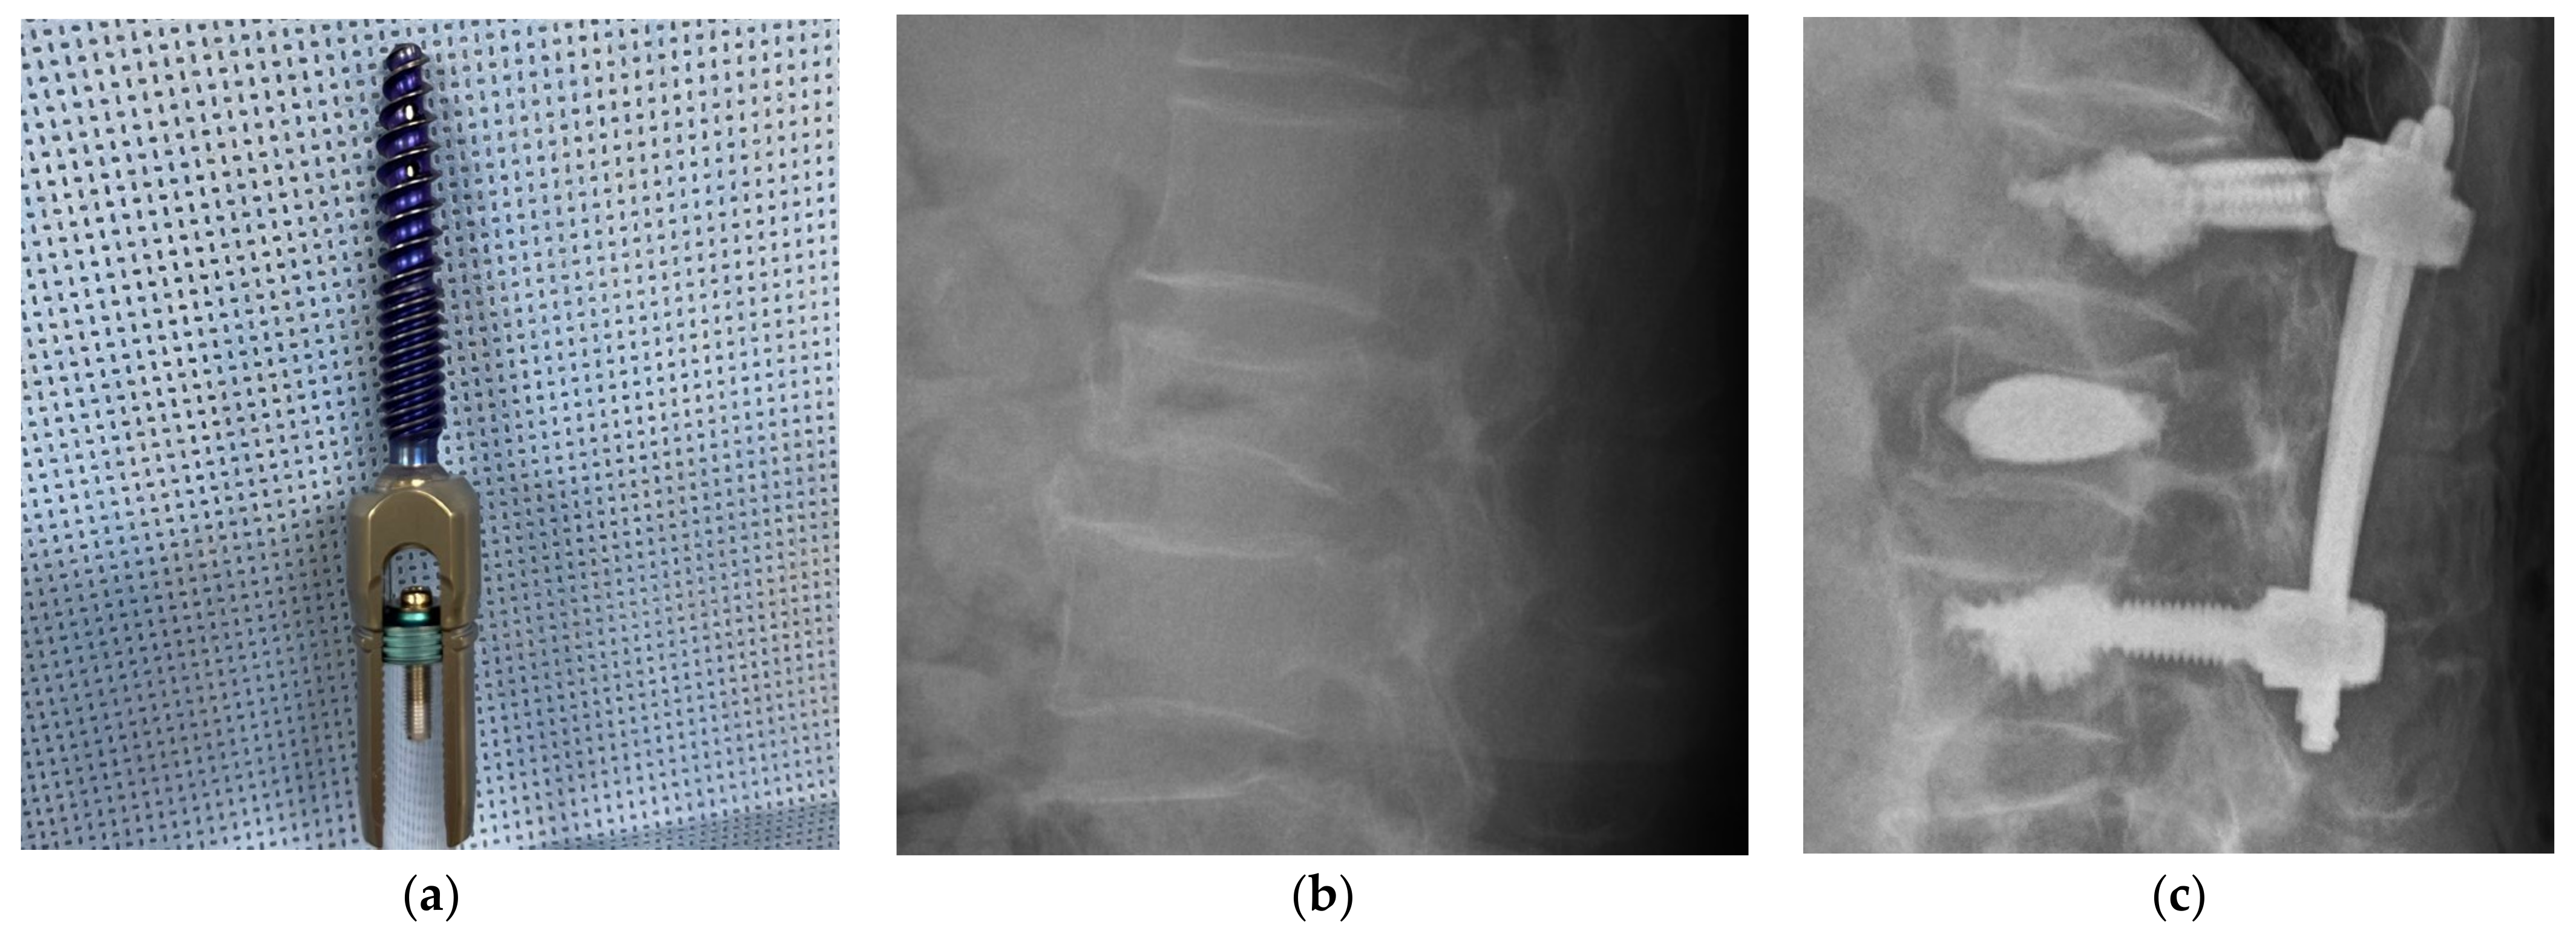

- Sung, S.; Kwon, J.-W.; Park, T.H.; Lee, S.-B.; Moon, S.-H.; Lee, B.H. Biomechanical Comparison and Three-Dimensional Analysis of Cement Distribution Patterns for Different Pedicle Screw Designs. BioMed Res. Int. 2022, 2022, 1–8. [Google Scholar] [CrossRef]

- Dai, F.; Liu, Y.; Zhang, F.; Sun, D.; Luo, F.; Zhang, Z.; Xu, J. Surgical treatment of the osteoporotic spine with bone cement-injectable cannulated pedicle screw fixation: Technical description and preliminary application in 43 patients. Clinics 2015, 70, 114–119. [Google Scholar] [CrossRef]

- Wang, Z.; Liu, Y.; Rong, Z.; Wang, C.; Liu, X.; Zhang, F.; Zhang, Z.; Xu, J.; Dai, F. Clinical evaluation of a bone cement-injectable cannulated pedicle screw augmented with polymethylmethacrylate: 128 osteoporotic patients with 42 months of follow-up. Clinics 2019, 74, e346. [Google Scholar] [CrossRef]